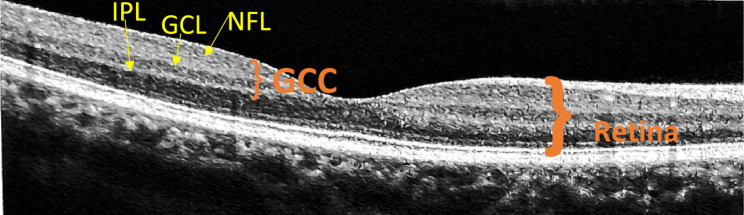

Background: To evaluate the ganglion cell complex thickness in patients taking oral hydroxychloroquine.

Methods: In this hospital-based, cross-sectional, non-interventional, comparative study, 87 eyes of 87 patients taking hydroxychloroquine were recruited. All the patients underwent complete ophthalmological evaluation along with dilated fundus examination. Patients were divided into two groups based on the duration of hydroxychloroquine intake: Group 1 (62 patients having duration of hydroxychloroquine intake < 5 years) and Group 2 (25 patients having duration of hydroxychloroquine intake ≥ 5 years). Age and gender-matched healthy volunteers with normal ocular findings were taken as controls. Average, superior, inferior GCC thickness, focal loss volume, and global loss volume were measured by RTvue XR Avanti SD-OCT.